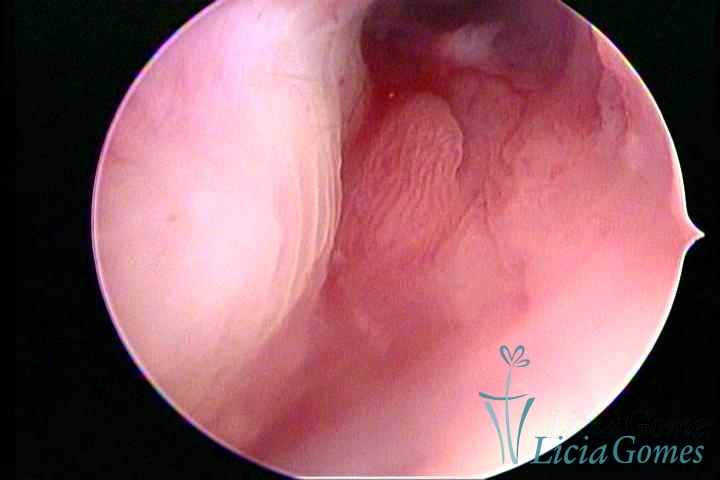

ENDOCERVICAL POLYPS

Benign tumors resulting from the reactive focal proliferation to inflammatory processes or hyperestrogenism situations, which may be sessile (with a large implantation) or stalked.